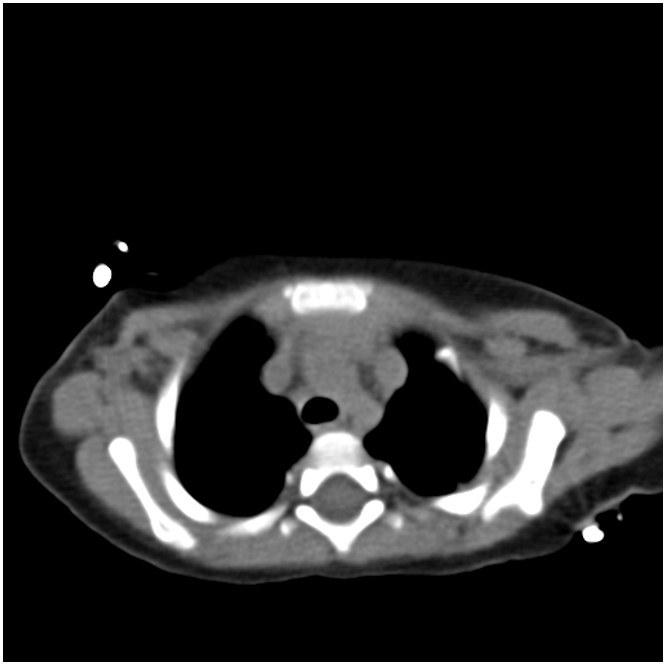

A 12-month-old boy presented for evaluation of recurrent bronchiolitis and hypoxemia. He was repeatedly admitted for acute respiratory failure at age 6, 9 and 11 months old. At 6 and 9 months of age he was positive for RSV but there was no clear infectious source in the third admission. He required oxygen support with all admissions. He had a normal echocardiogram at 2 and 11 months of age. At 13 months old he was seen by his pediatrician and noted to have an oxygen saturation of 88% on room air with no clear inciting illness which prompted another admission and pulmonary consultation. CT of the chest demonstrated the following:

What abnormality does the above chest CT reveal? What is the next best test to evaluate this abnormality?

B. Persistent left superior vena cava and cardiac catheterization